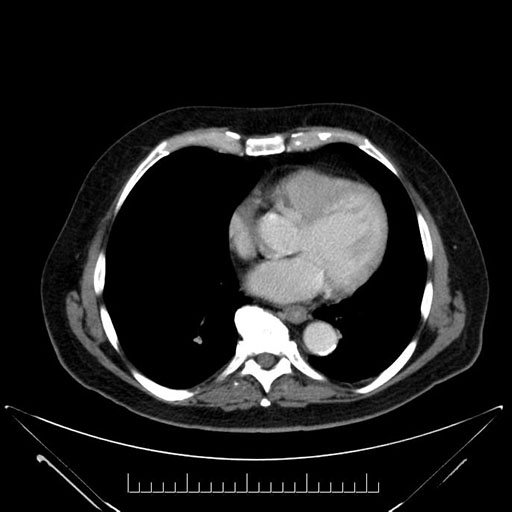

Axial - 3 months prior

Axial - stented

Coronal - stented